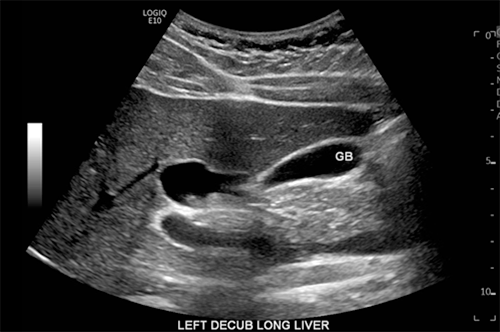

The patient is an 18-year-old male with glucose-6-phosphate-dehydrogenase deficiency that initially presented to the emergency room with epigastric pain. A CT abdomen and pelvis with contrast was obtained, demonstrating dilatation of the gallbladder and a cystic structure directly adjacent to or contiguous with the gallbladder (Figure 1). The patient's symptoms resolved, and he was sent home with clinical follow-up.

Figure 1. Preoperative CT Scan Demonstrating Choledochal Cyst. Published with Permission